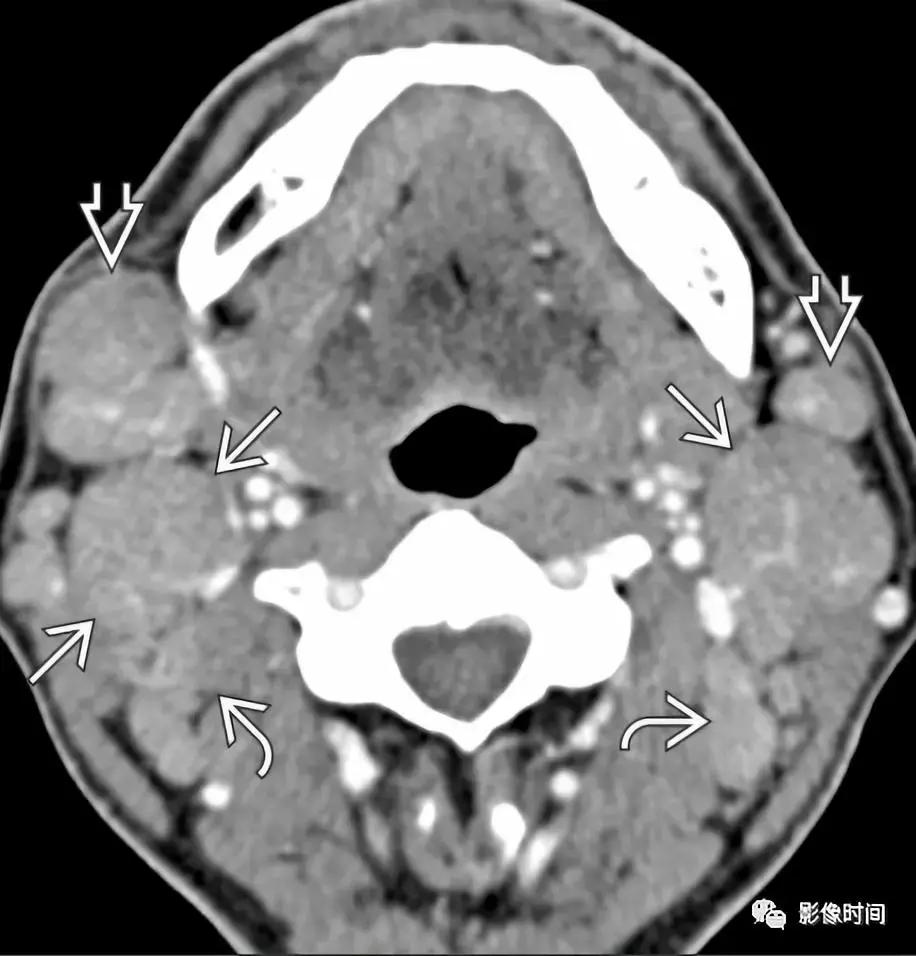

轴位增强 CT 显示双侧舌骨上颈部多发淋巴瘤,不均匀强化,没有坏死。